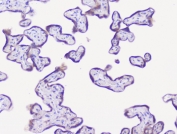

NSE Antibody Human Pancreatic Cancer IHC. Immunohistochemistry staining of FFPE human pancreatic cancer with NSE antibody at 1ug/ml. HIER: boil tissue sections in pH6, 10mM citrate buffer, for 10-20 min followed by cooling at RT for 20 min.